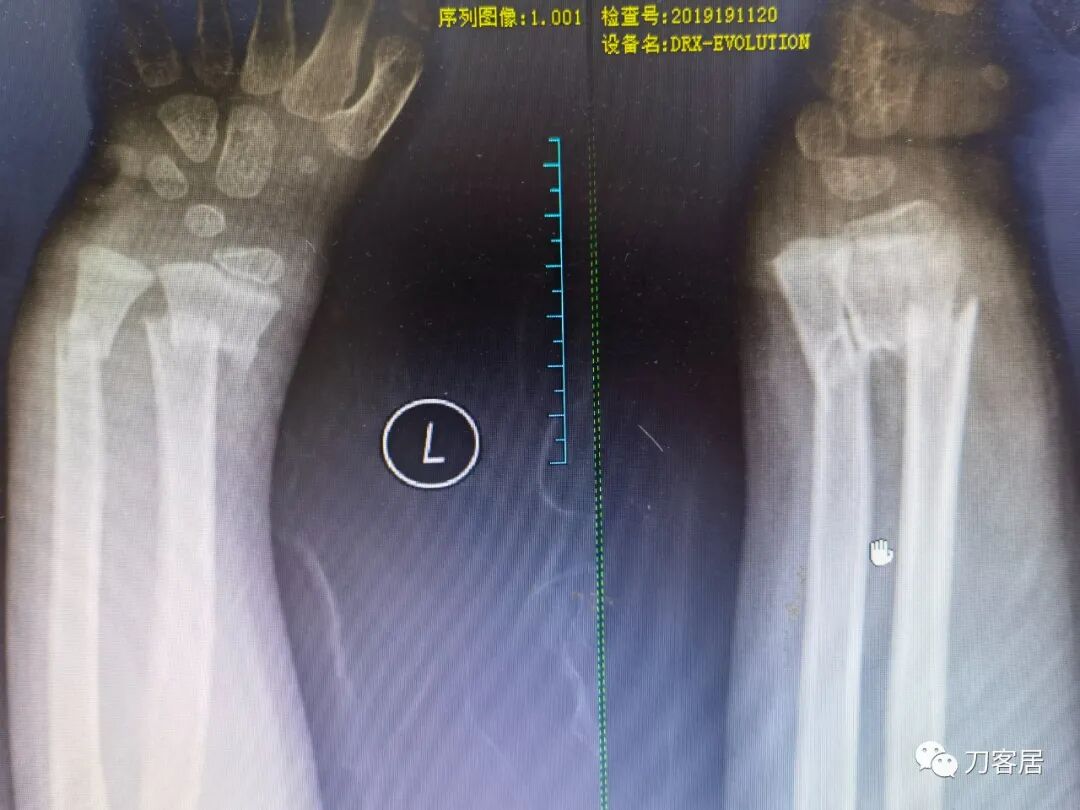

2021年7月21日,在中华骨科网儿童骨科病例讨论群里,看到了几张图片,是某仁慈医院的一位手外科医生做的手术,被某地器械厂家发在朋友圈里炫耀,有小儿骨科医生看不过去,就发群里请大家评论,引起众多小儿骨科医生的批评。

下面是这个6岁孩子,尺桡骨远端双骨折的术前及术后片子和外观照片。

1.  这是一个很简单的6岁儿童无移位的尺桡骨远端骨折。没有皮肤损伤,没有移位,没有骨折碎块儿。

2.  这个骨折处理起来也很简单,单纯的打石膏托或者中医的小夹板,或者正规的包括腕关节和肘关节的管型石膏外固定4周即可治愈该骨折。实在不行,如果这个孩子比较听话,不太调皮的话,用一本书,一个三角巾悬吊固定4周,都可以治愈该骨折。但是给这个患者用外固定架做了手术,而且桡骨远端的几颗克氏针距离骨折线太近,其中一枚克氏针进入到骨折间隙内。从这个术中图片来看,术者的外固定手术技术也有待于进一步的提高。毕竟术者应该还很年轻。从X线片来看,前臂及手的尺侧有不透光影,应该还使用了外固定石膏绷带托,而且我猜测应该是高分子的石膏绷带托,这个是纯属猜测,不一定是对的,不过如何解释前臂尺侧的不透光影呢?如果真是用了石膏绷带外固定的话,那为啥要做手术呢?外固定架术后就不该再用石膏绷带托辅助了。